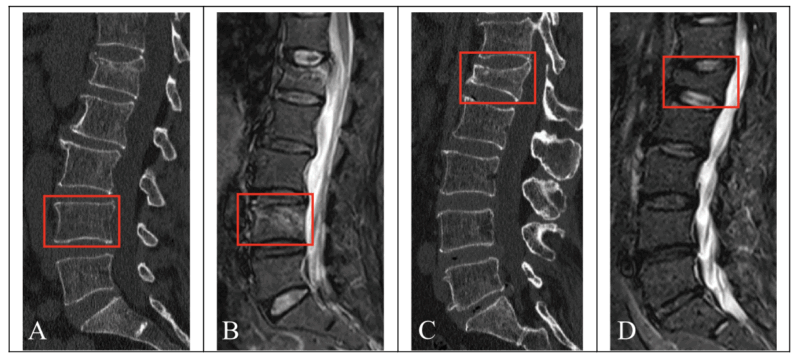

新鮮な骨折(骨折してから概ね2-3カ月以内)では, MRIで椎体が白く写りますが(上図B), 旧い骨折(骨折してから概ね4カ月以上経過)では, 椎体が潰れていても(上図C), MRIでは椎体が白く写らずに, 骨折のない椎体と同じような色合いに写るようになります(上図D).

撮像されたX線写真を見たところ, 胸椎と腰椎が3箇所で潰れて骨折していましたが, MRIでは骨折の所見がなく, 数ヶ月以上前の旧い骨折であると診断しました. 骨盤の骨にも異常はなかったので, 打撲傷と診断して, 鎮痛薬を処方して, 帰宅していただきました.